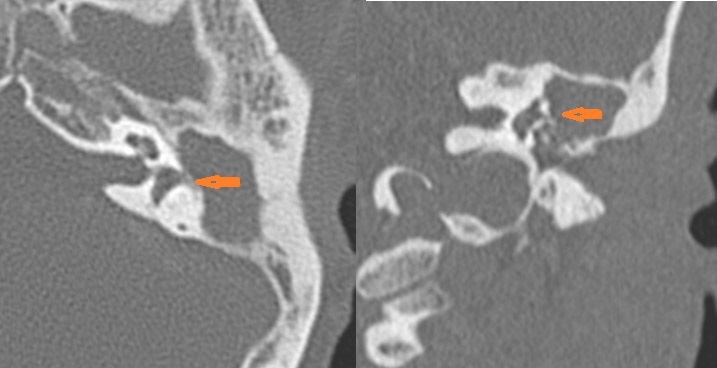

The ossicles, in particular the incus long process, the incudostapedial joint and stapes are eroded or displaced. [Yes/No]